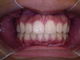

Casos clínicos - Distração Osteogênica

Paciente 1